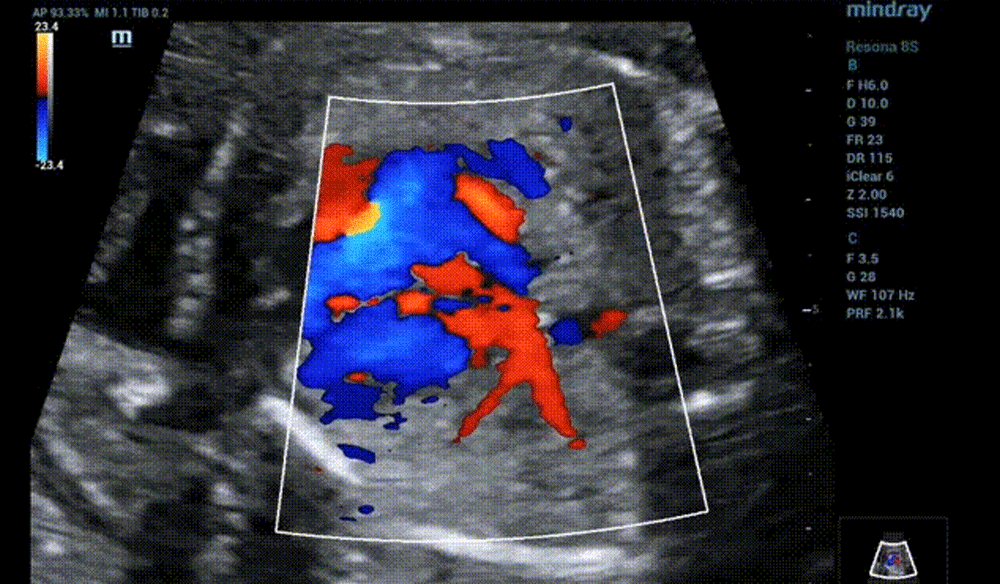

Pulmonary vein blood flow

• Color Doppler shows the blood from LSPV and LIPV flowed through the coronary sinus and directly flowed into the right atrium, which crossed the right superior and right inferior pulmonary veins in a dislocation rather than confluence.

• Four chambers view of color doppler seems to show that all pulmonary veins return to the left atrium. Actually, LSPV and LIPV only brush below the LV rather than drain into the left atrium.